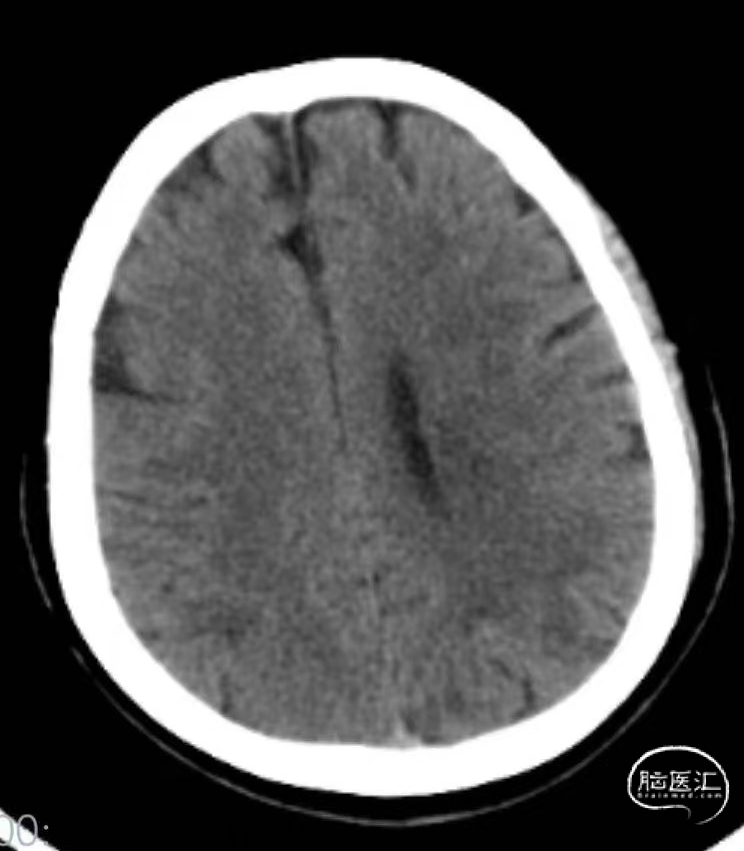

➤2024.2.28 头颅MRI+MRA

左额顶叶/左枕叶亚急性期脑梗死,左侧大脑中动脉M1段重度狭窄。